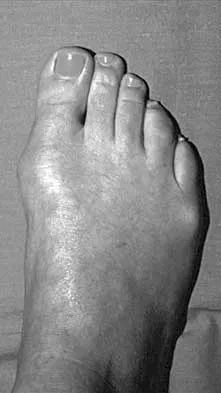

What complication is frequently associated with the Weil lesser metatarsal osteotomy (distal, oblique) in the treatment of claw toe deformities?

Detailed Explanation